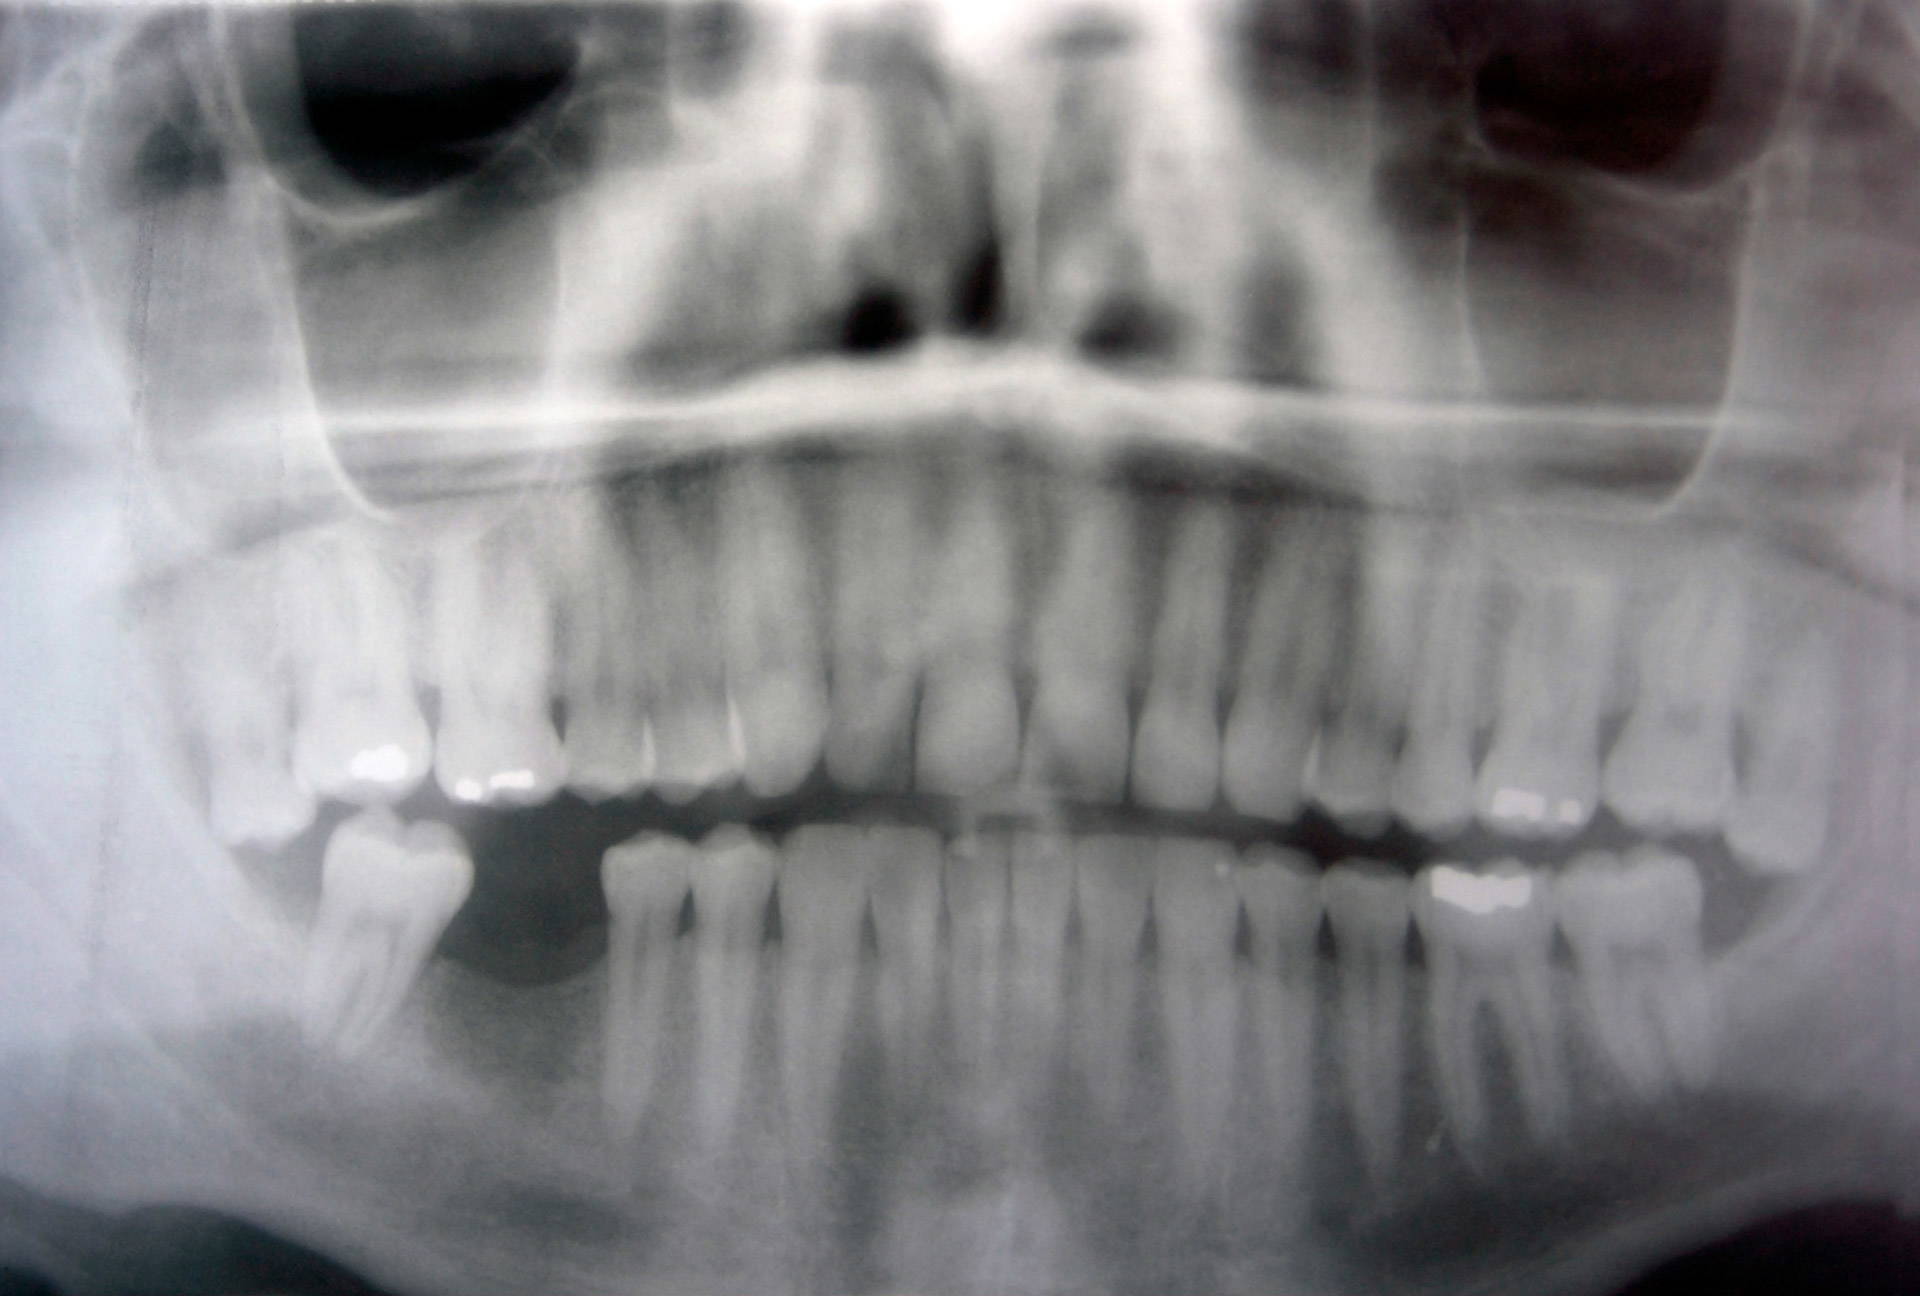

To prepare a tooth for a crown, each tooth has to be assessed clinically, which may also include an x-ray or scan. The tooth is then shaped and slimmed down to make space for the crown to fit on top. An impression or scan is completed, which is sent to the lab so that they can begin to make your personalised crown. After around 2 weeks, the crown(s) come back and are fitted. Whilst waiting for the final crowns to come back, a temporary crown will be made(we wouldn’t let you leave and spend two weeks smiling with a slimmed down tooth!). As natural tooth structure is taken away there is always a risk that the tooth (if already healthy) may develop some sensitivity which can lead to root canal or in some extreme cases an extraction, this is uncommon and using modern techniques we have done our best to lower the chance of this occurring.